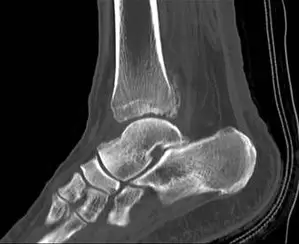

CT scan and Xray sagittal views of severly displaced posterior tibial malleolar fracture with comminution. This type of injury can cause significant problems in the future with disability if not treated with surgery to reduce the fracture and fixate.

CT scan sagittal views of minimal displaced posterior tibial malleolar fracture.